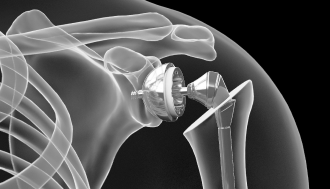

회전근개봉합술